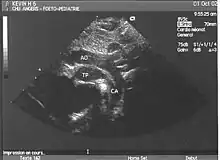

Aspects échographiques avant la naissance

Les structures strictement intra cardiaques étant habituellement normales, le diagnostic ne peut être évoqué sur l'incidence dite des "4 cavités". Il nécessite obligatoirement (et logiquement) une exploration des gros vaisseaux passant par d'autres plans de coupe plus haut situés dans le thorax.

- le signe d'appel habituel est la perte du croisement des gros vaisseaux. Normalement, l'aorte et le tronc pulmonaire se croisent peu après leur sortie du cœur. Il est donc impossible de dérouler les deux vaisseaux sur un même plan de coupe. Quand l'aorte est vue longitudinalement, le tronc pulmonaire n'apparaît qu'en section transversale ("aorte en long, tronc pulmonaire en rond") et vice-versa. Dans la D-TGV simple, la plus fréquente, les vaisseaux ont un trajet parallèle et peuvent donc être visualisés longitudinalement simultanément.

- la confirmation est obtenue par l'analyse des gros vaisseaux et de leurs connexions aux ventricules. L'aorte est caractérisée par le fait qu'elle décrit une crosse, donne naissance aux vaisseaux à destinée céphalique et est le vaisseau qui monte le plus haut dans le thorax. Le tronc pulmonaire est caractérisé par sa bifurcation précoce en deux branches, les artères pulmonaires droite et gauche. Sur un cœur par ailleurs normal, le ventricule droit est situé en avant et à droite du ventricule gauche, le tronc pulmonaire est donc le vaisseau le plus antérieur. La TGV se caractérise par la position antérieure du vaisseau qui décrit la crosse et donne les vaisseaux céphaliques : l'aorte.